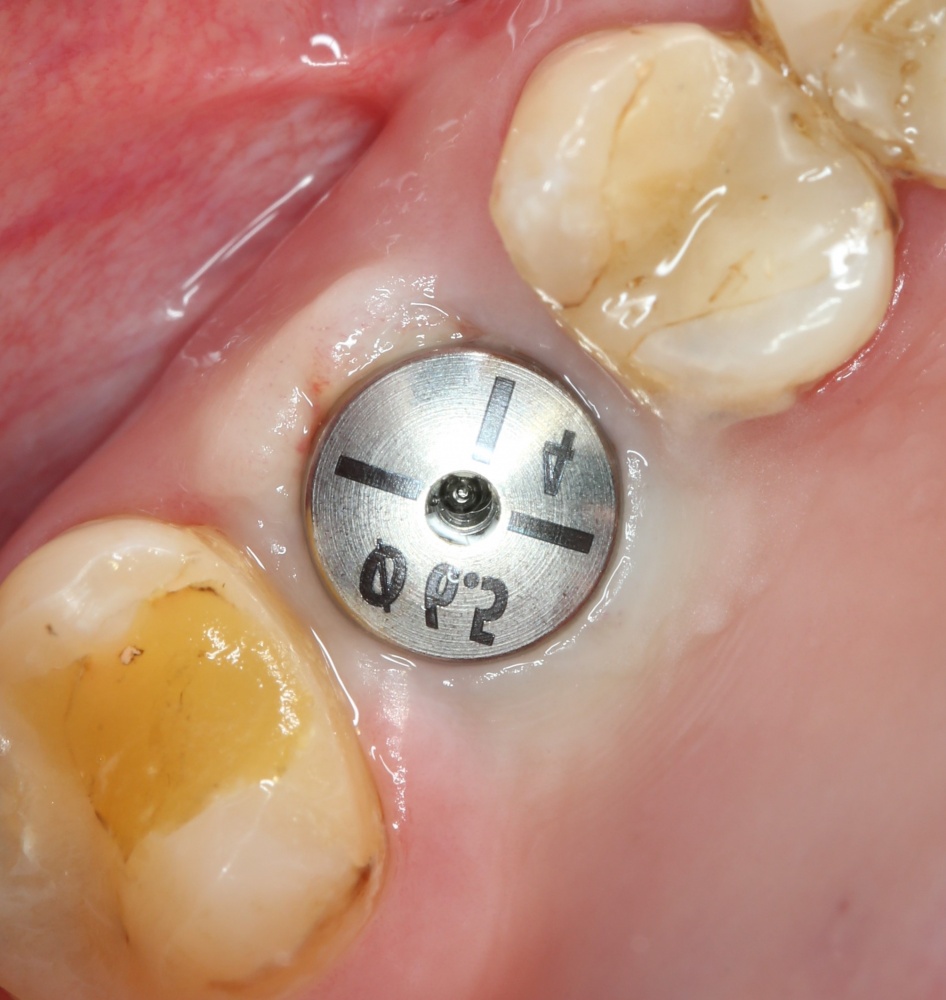

Устанавливаем формирователи десневой манжеты. Сегодня я называю эту процедуру не менее важной, чем любой другой этап имплантологического лечения:

И швы. Просто швы. Никаких дополнительных процедур.

Если честно, то сейчас бы я использовал другой шовный материал и другой тип швов. Одно неизменно, — и я об этом много раз говорил, — самая широкая часть формирователя десны должна находиться на уровне десны. Так, чтобы эффективно отрабатывать т. н. «биологическую ширину».

Через неделю я снял швы, а мой коллега Андрей Карнеев (дело было еще в НИЦ) приступил к изготовлению протезов. На это ушло полторы недели: